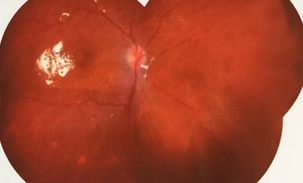

独眼,视网膜全脱离已成窄漏斗状、陈旧性葡萄膜炎、瞳孔后黏连无法散大,且并发白内障使得视网膜周边部细节情况无法看清,左眼已无光感,角膜白斑,瞳孔闭锁,还填充着硅油。右眼既往葡萄膜炎病因不清,一年中发病3、4 次都是用激素医治。左眼多年前是“天那水”溅入后又发生玻璃体出血手术后……令人担心的是这次我们克服重重困难救治全部脱离的视网膜 后,可能会面对长期慢性葡萄膜炎、长期药物医治的继发性高眼压,以及葡萄膜炎的再次复发等,稍有不慎就是不逆性致盲了。

手术室外,是家属们焦灼的等待。手术室内,是赵院长肩负重任带领大家紧张抢救。这是一场与时间赛跑、与病情赛跑,从黑暗到光明的抢救医治。赵铁英院长全神贯注、时而需要屏住呼吸如履薄冰般地操作、目不转睛同时双脚控制显微镜和机器参数,双手紧密配合,在如同混浊的海底世界的眼球腔内修复重建……

后,终于新旧病变处理完毕,展平复位了即将全部粘连在一起的视网膜,手术获得了 !没有下夜班仍继续在医院组织会诊参加手术的助手龙飘飘医生也长舒了一口气说:挽救了一个眼,挽救了一个人,挽救了一个家庭!